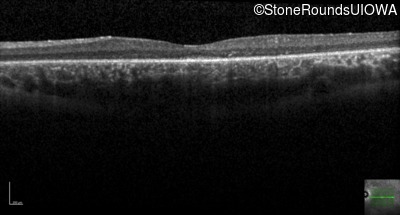

Optical Coherence Tomography - Left - 20/40 +2

Exemplar / OCT Stack